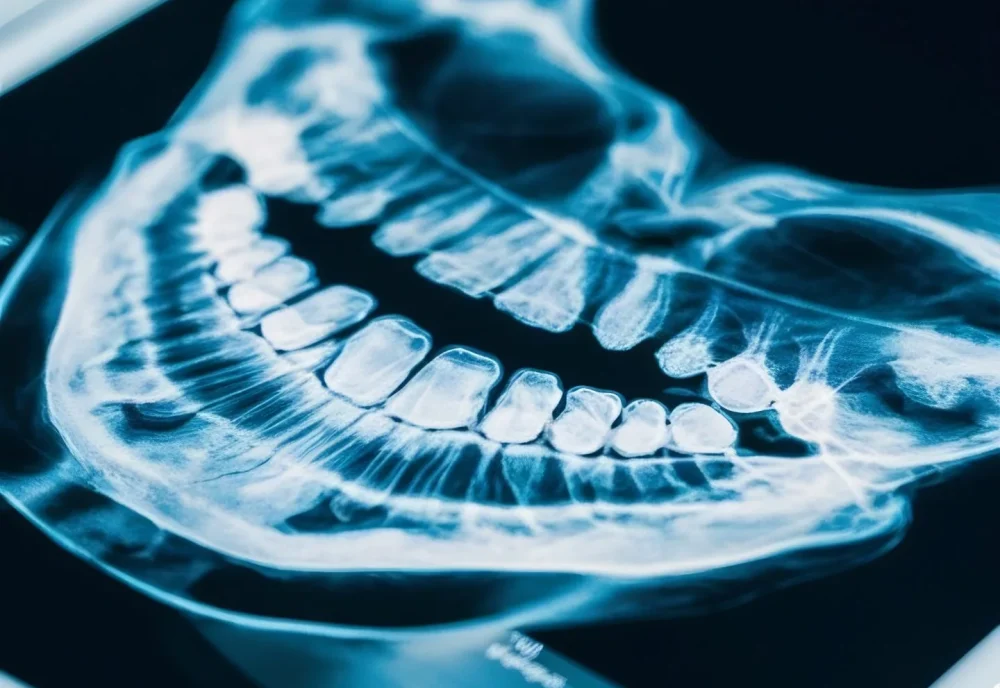

الرئيسية /الأشعة المقطعية ثلاثية الأبعاد

هي فحص متطور يُصوِّر أسنانك، عظام الفك، والأعصاب بصورة ثلاثية الأبعاد و بدقة عالية.

✅ قبل زراعة الأسنان.

✅ لتشخيص مشاكل الجذور أو الأكياس.

✅ لتقييم الأسنان المدفونة (ضروس العقل).

✅ عند التخطيط لتقويم الأسنان.

✅ عند وجود آلام غامضة في الفك.